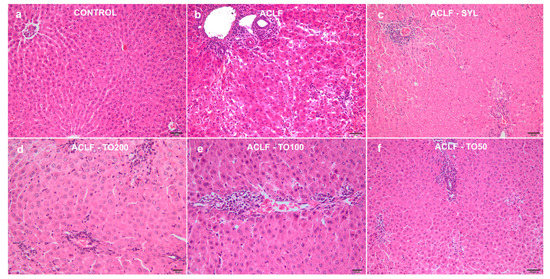

3.3. Histological Assessment

| Groups | Portal Inflammation | Periportal Degeneration/ Necrosis | Intralobular Degeneration/ Necrosis | Fibrosis | HAI | 3NT |

|---|---|---|---|---|---|---|

| ACLF-TO200 | 1.60 a,b,c ± 0.89 | 2.20 a,b,c ± 0.10 | 1.00 a,b,c ± 0.01 | 1.20 a,c ± 0.10 | 5.80 a,c ± 1.92 | 1.40 a,b,c ± 0.55 |

| ACLF-TO100 | 2.20 a,b,c ± 0.10 | 2.60 a,b,c ± 0.89 | 1.40 a,b,c ± 0.89 | 1.00 a,c ± 0.10 | 7.20 a,b,c ± 1.10 | 1.40 a,b,c ± 0.55 |

| ACLF-TO50 | 2.60 a,b,c ± 0.89 | 2.20 a,b,c ± 1.10 | 2.20 a,b,c ± 1.10 | 1.00 a,c ± 0.10 | 8.00 a,b,c ± 1.41 | 1.80 a,b,c ± 0.45 |

| ACLF-SYL | 1.00 a,b ± 0.00 | 0.60 a,b ± 0.55 | 0.80 a,b ± 0.45 | 0.40 a,b ± 0.55 | 2.80 a,b ± 0.45 | 1.20 a,b ± 0.45 |

| ACLF | 3.60 a,c ± 0.55 | 4.80 a,c ± 0.84 | 3.60 a,b ± 0.55 | 1.00 a,b ± 0.10 | 12.80 a,b ± 1.64 | 2.40 a,b ± 0.55 |

| Control | 0.40 ± 0.55 | 0.00 ± 0.00 | 0.00 ± 0.00 | 0.00 ± 0.00 | 0.20 ± 0.45 | 0.00 ± 0.00 |